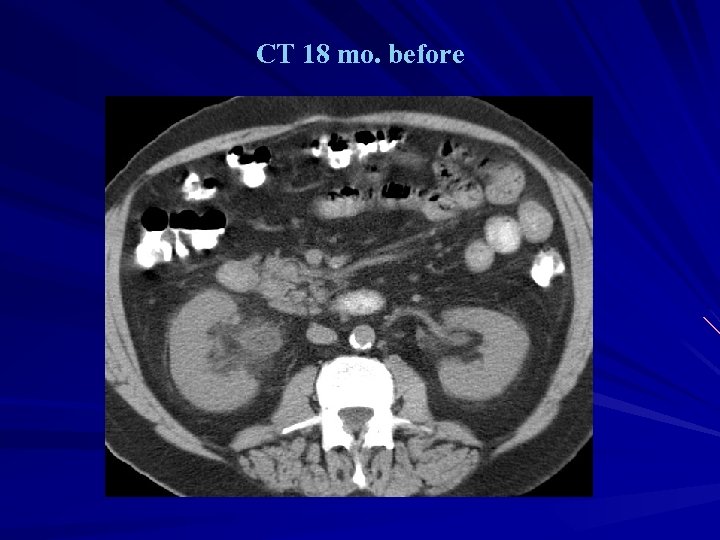

v 68 Y. O. man v 6 years post bladder replacement d/t TCC v 6 months intermittent macrohematuria

CT 18 mo. before